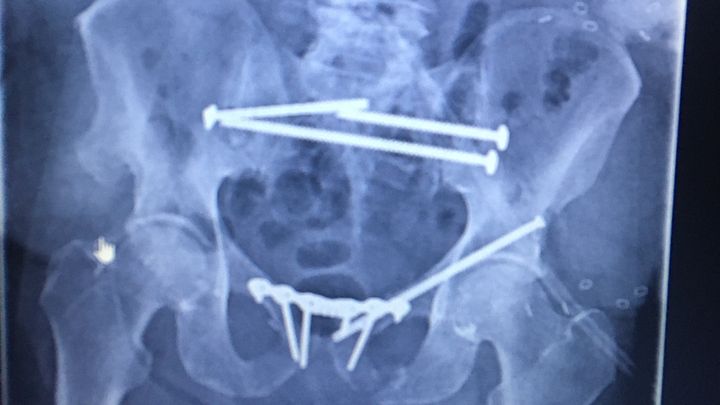

I was run down by an uninsured inattentive driver on Aug 3, 2020. I spent 4 months in the hospital. My employer of 20 years denied long-term disability, so costs are out of pocket. I'm awaiting yet another procedure at the Mayo Clinic. Transportation will be an issue. Every little bit helps. Thank you.